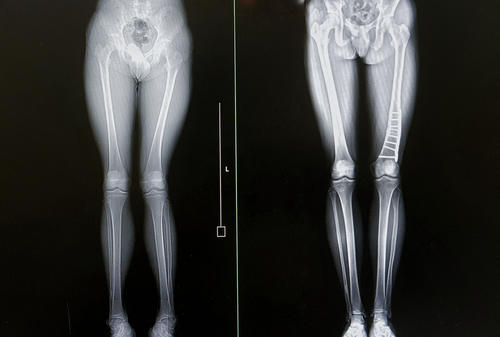

Фотогалерея

Основным инструментальным методом диагностики перелома костей является рентгенография. Процедура позволяет быстро выявить нарушение целостности костных структур и в кратчайшие сроки приступить к нужному лечению. На рентгенограмме можно увидеть место повреждения и его характер, расположение костных фрагментов. Признаками перелома является расхождение, смещение костей, изменение суставной полости.